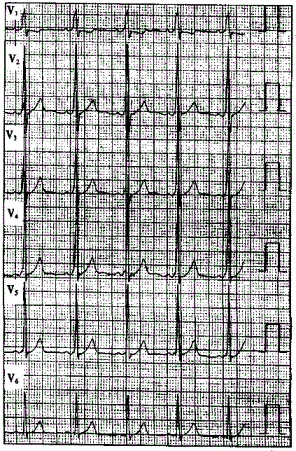

问题 患者男性,40岁,多次发作心悸,心电图一-见下图,显示为预激图形。 ? ? 为了解心悸是否与预激有关,有意义的检查是

选项 A.常规心电图 B.运动心电图 C.动态心电图 D.食管心房调搏 E.超声心动图

答案 D

解析 :食管心房调搏可以诱发心动过速并确定心动过速的发生机制该心电图显示V导联delta波向上,旁路位于左侧;Ⅱ、Ⅲ、aVF导联delta波向上,提示旁路位于左侧壁;当旁路前传有效不应期<270ms或预激综合征合并心房颤动时最短RR间距≤240ms时,提示为高危旁路;逆向型房室折返性心动过速的折返途径为:心房→旁路→心室→房室结→心房